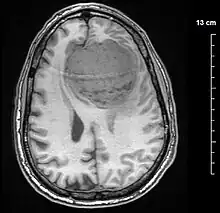

A meningioma that previously had been operated on, with surrounding edema

MRI image of a meningioma with contrast

Meningiomas are visualized readily with contrast CT, MRI with gadolinium,[22] and arteriography, all attributed to the fact that meningiomas are extra-axial and vascularized. CSF protein levels are usually found to be elevated when lumbar puncture is used to obtain spinal fluid. On T1-weighted contrast-enhanced MRI, they may show a typical dural tail sign absent in some rare forms of meningiomas.[17]